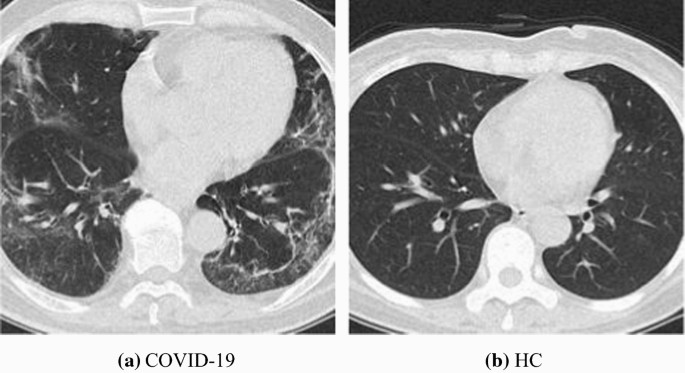

Table 3 Image size and storage per image at each preprocessing step Figure 2 shows two samples of our collected and preprocessed dataset \({S}_{5}\), from which we can clearly observe the clinical biomarkers of COVID-19. Cui et al. [19] reported the preliminary CT findings of COVID-19 in their publication. Tuncer et al. [20] used chest CT images, and then developed a local binary pattern and iterative ReliefF algorithm. There are more open publications that show it is feasible to develop effective AI systems based on CCT images.